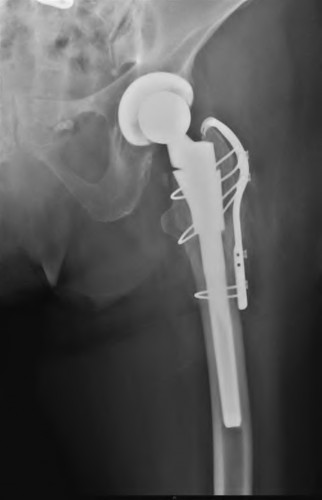

A 72-year-old female falls and sustains a periprosthetic femur fracture around her cementless total hip arthroplasty. Radiographs reveal a fracture extending just distal to the tip of the stem. The stem is radiographically loose, but there is excellent proximal and distal bone stock. According to the Vancouver classification, what is the fracture type and the recommended surgical treatment?

A 75-year-old female sustains a fall 5 years after a cementless THA. Radiographs show a periprosthetic femur fracture occurring around the stem tip. Intraoperative assessment reveals the stem remains firmly fixed in the metaphysis, and the proximal bone stock is adequate. According to the Vancouver classification, what is the fracture type and the standard recommended treatment?

A 72-year-old female presents with acute thigh pain and an inability to bear weight after a minor fall, 10 years post-THA. Radiographs demonstrate a fracture around the tip of the well-fixed femoral stem, extending into the diaphysis. The bone stock proximally remains intact. Which principle must be strictly adhered to during the surgical fixation of this fracture?

A 78-year-old female sustains a periprosthetic femur fracture 10 years after a cemented THA. Radiographs show a fracture around the tip of the stem with a loose femoral component and poor proximal bone stock, but adequate diaphyseal bone.

A 75-year-old female sustains a periprosthetic femur fracture around a cemented polished taper slip stem. Radiographs demonstrate a fracture around the tip of the stem. The stem is radiographically loose, but the proximal bone stock is excellent (Vancouver B2).